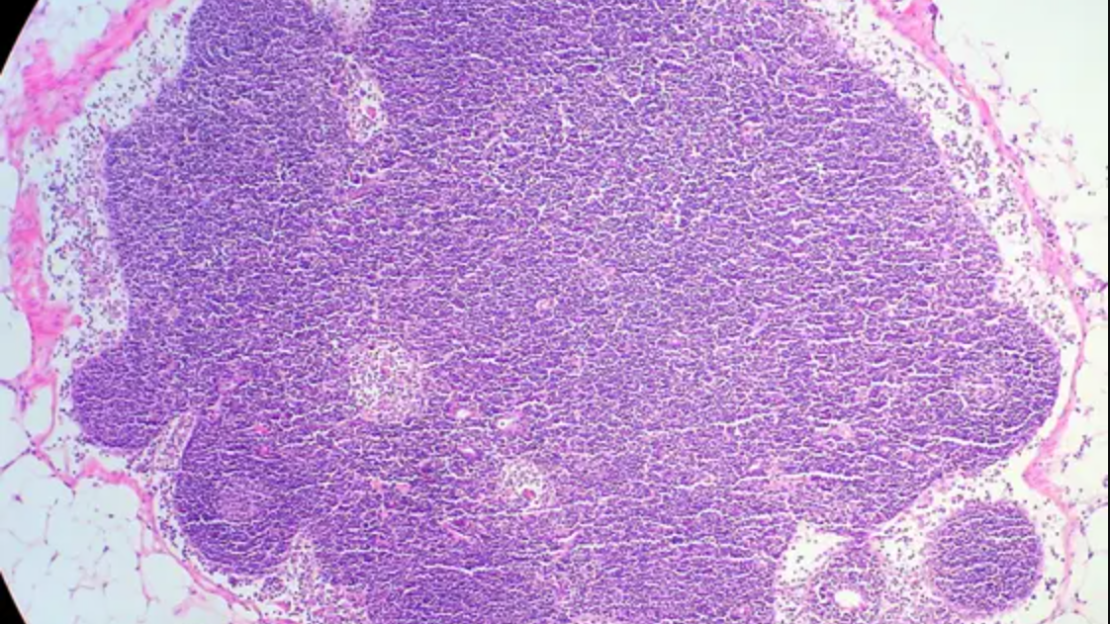

In B-cell lymphomas, the internal organization of the lymph node tissue is disrupted in very different ways depending on the disease: While in slow-growing lymphomas, such as follicular lymphoma (FL), the basic tissue structure remains intact, the spatial organization in aggressive lymphomas, such as diffuse large B-cell lymphoma (DLBCL), breaks down completely. Why these typical growth patterns arise has been largely unclear until now.

The data show that stromal cells are the “architects” of the lymph node. The researchers were able to demonstrate that key signaling pathways in specialized stromal cells undergo fundamental changes in lymphoma, causing the spatial organization of the lymph node to gradually collapse. These changes in stromal cells are reflected in the growth patterns of lymphomas: While in FL the relative sizes of B-cell follicles and T-cell zones shift, the areas remain largely spatially separated; in DLBCL, however, key regulatory signals—and thus the tissue structure—are largely lost.